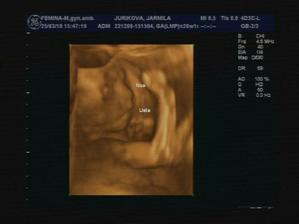

18.2. - Poradňa, našťastie všetko v poriadku, máme 334g a bude to... NINKA!!

14.4.2010 - Poradňa, všetko OK, máme 1,2 kg. 🙂)) A je to stopercentne dievčatko. 🙂)))